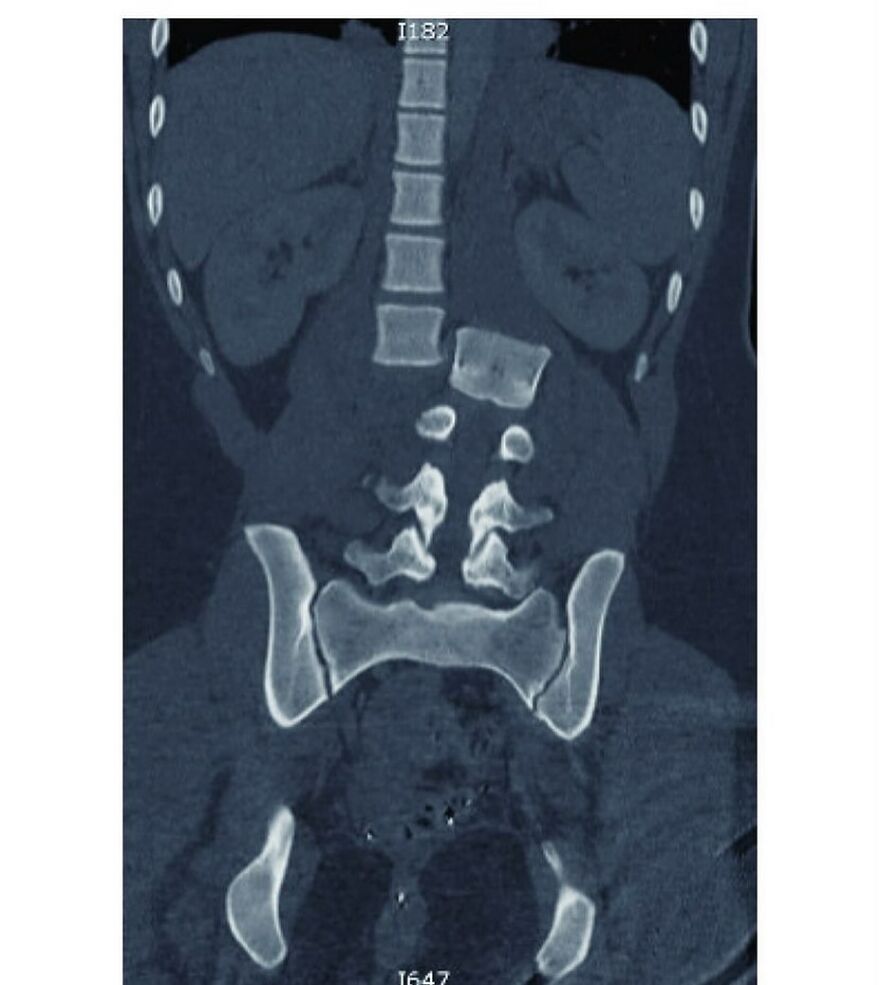

Foot binding (also known as Lotus foot) was the custom of applying tight binding to the feet of young girls to modify the shape and size of their feet

It was practised in China from the Song dynasty until the early 20th century, and bound feet were considered a status symbol as well as a mark of beauty

Foot binding limited the mobility of women, and resulted in lifelong disabilities for most of its subjects, although some women with bound feet working outdoors have also been reported

The age in which the binding happens differs in areas, but happend between 4 and 8 years old. The process takes about two years and is extremely painful: bones in the foot are broken, and replaced under the foot. All this time, girls must keep walking to put pressure on the bind foot, and achieve the ideal shape and length. 1 in 10 girls would die during the binding because of complications, and other complications happend quite regurlaly: not all binded woman could walk properly because of binding gone wrong. The ideal length of a bound foot would be around 7 cm. Kind of the size of a thumb. Without bound feet woman were unmarriable. Woman with unbound feet often became maids or worse. Source: my head, because of books I've read. Edit: grammar mistake